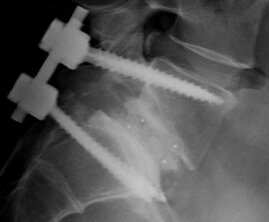

Artrodesi Spinale (Fusione): consiste nella fusione di due o più vertebre adiacenti per stabilizzare la colonna, utilizzando materiali come barre metalliche, viti peduncolari, gabbie intersomatiche e innesti ossei.

Decompressione nervosa: consiste nella rimozione di strutture ossee (laminectomia) o discali che comprimono i nervi spinali.

Riduzione dello scivolamento: in alcuni casi, si tenta di riposizionare la vertebra scivolata prima della fusione.

Attraverso tecniche minimamente invasive e approcci chirurgici moderni con incisioni ridotte si può ridurre il tempo di recupero e le complicanze post-operatorie.